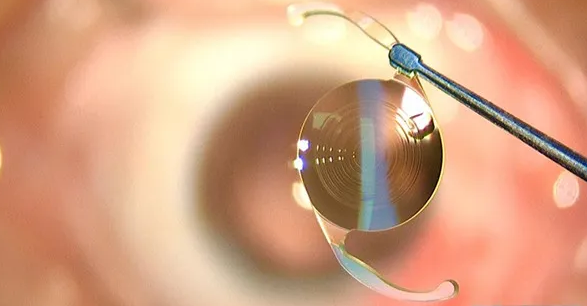

8月14日上午,鲍捷主任为扎西先生成功实施了右眼白内障超声乳化术+人工晶体植入术,手术不到10分钟就完成了。

术后第二天,医务人员为扎西先生拆掉右眼纱布,经过测试,他右眼的视力由术前的0.25提升到了现在的0.8,扎西先生表示非常满意。鲍捷主任表示:“随着时间推移,他应该还会恢*得更好。”

据张学进副院长介绍,爱尔康三焦点人工晶体是刚刚于国内面世的第二款三焦点人工晶体,可以为患者术后提供远中近全程视力,尤其是可以提供患者生活所需的60cm中距离,可以满足日常生活中所需要的视力范围。可以帮助白内障患者解决看远(比如走路,旅游),看中(比如吃饭、看电脑,做家务),看近(比如读书,看报,看手机等)的问题,提*脱镜率。